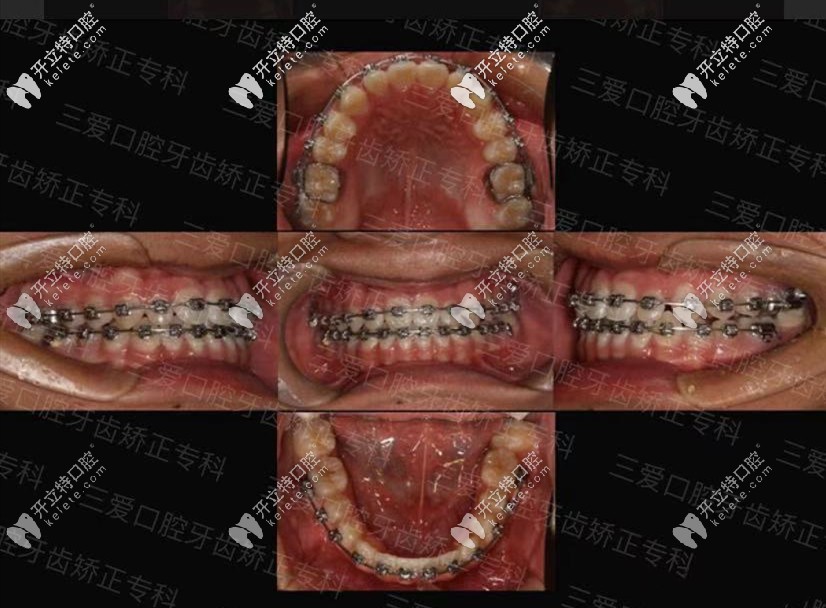

地包天矯正前后對比圖

↑地包天在三愛口腔矯正案例